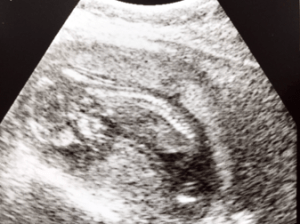

Left: Our precious little one and her perfect spin, and

FINDING OUT THE SEX: We had it scheduled to find out the sex somewhere around twenty weeks. Although, we went into an appointment to see my doctor around eighteen weeks and we walked into the big room set up with ultrasound equipment. She had me lay down to look at the baby’s heartbeat and make sure everything looked good. My husband and I asked, “Is there anyway you can tell if it is a boy or a girl?” We expected her to answer our question, but she surprised us with her response. She knew that we were anxious to know the sex… but instead of answering our question with a ‘yes’ or a ‘no’, she replied, “It’s a GIRL!” There was no warning or build up… I quickly looked over at my husband’s face and we were shocked and excited! I had a gut feeling I was having a girl, but I never expected it to be true because of our family. I have three brothers, my mother has one brother, my dad has three brothers, and I have four nephews… this is going to be one spoiled little baby girl!